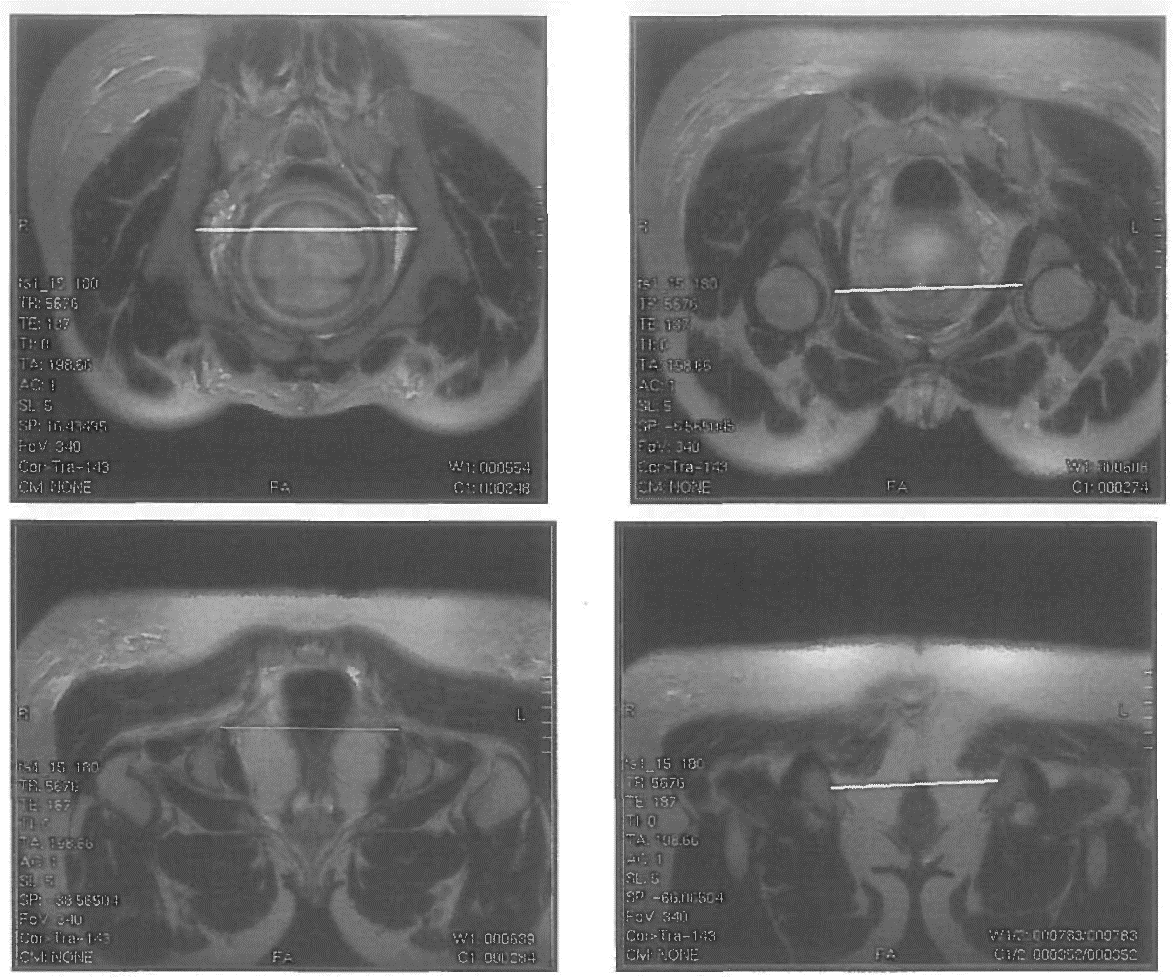

4. Т2ВИ (SSFSE/HASTE) в косой поперечной плоскости (плоскость входа в таз) толщина среза 3-4 мм, матрица квадратная не менее 320x320, поле обзора 300-340 мм томограммы позиционируют как показано на рис. 1 с использованием полученных сагиттальных срезов параллельно linea innominata. На полученных томограммах измеряют поперечные размеры таза: наибольший размер входа, широкой части, межостный, битуберозный (рис. 4).

image

Рисунок 4. Т2ВИ в косой плоскости. А - наибольший диаметр входа (расстояние между наиболее удаленными точками безымянных линий костей таза). Б - поперечный диаметр широкой части полости (диаметр полости таза, лежащий на линии, проходящей через центры головок бедренных костей). В - межостный размер или поперечный размер узкой части полости таза (расстояние между вершинами седалищных бугров). Г - битуберозный размер или поперечный размер выхода (расстояние между шероховатостями седалищных бугров)